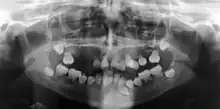

| Preoperative panoramic radiographs showing features of dentin dysplasia type I | |